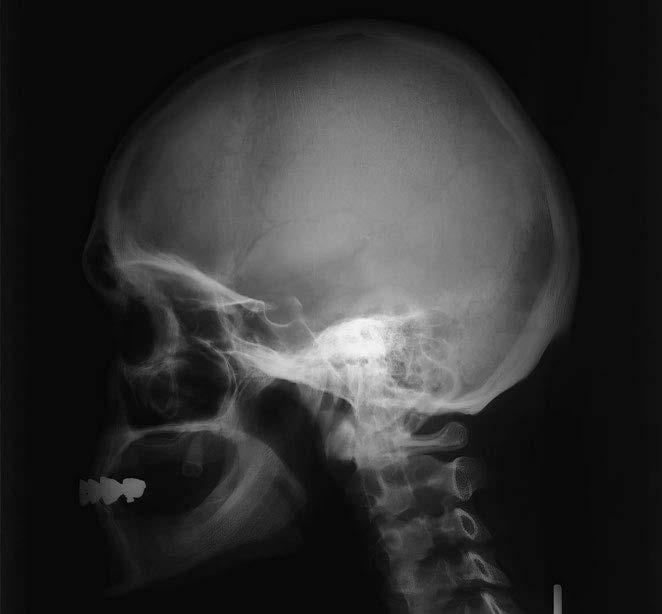

1 lamina externa

2 diploe

3 lamina interna

4 sutura coronalis (šev korunový)

5 sulcus arteriae meningeae mediae

6 sinus frontalis (dutina kosti čelní)

7 fossa hypophysialis (jamka tureckého sedla pro hypofýzu)

8 ala major ossis sphenoidalis (velké křídlo kosti klínové)

9 sutura lambdoidea (šev lambdový)

10 lamina cribrosa

11 processus clinoideus anterior (přední kuželovitý výběžek)

12 processus clinoideus posterior (zadní kuželovitý výběžek)

13 os nasale (kost nosní)

14 sinus sphenoidalis (dutina kosti klínové)

15 os zygomaticum (kost lícní, laterální stěna orbity/očnice)

16 clivus

17 cellulae ethmoidales (etmoidální sklípky, dutinky kosti čichové)

18 pars petrosa ossis temporalis (pyramida / kost skalní kosti spánkové)

19 sinus maxillaris (dutina horní čelisti)

20 porus acusticus externus (otvor zevního zvukovodu)

21 processus coronoideus mandibulae (krkavčitý výběžek dolní čelisti)

22 foramen magnum

23 processus zygomaticus (lícní výběžek)

24 palatum durum (tvrdé patro)

25 nasopharynx (nosohltan)

26 palatum molle (měkké patro)

27 mandibula (dolní čelist)